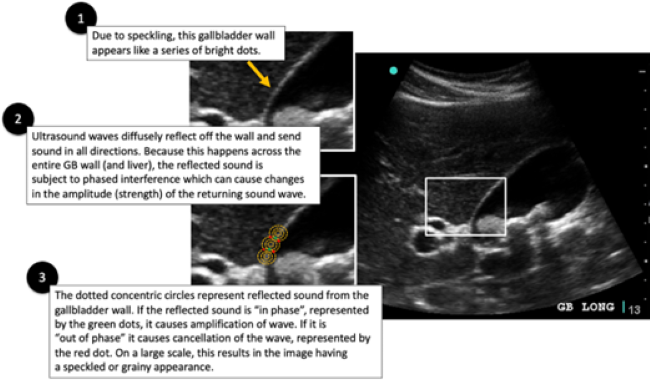

The result of using speckle reduction algorithms leads to ultrasound images appearing “smoother” with better demarcation of tissue borders. However, speckle reduction comes at a price with the introduction of a new artifact: image adaptive artifact. See Figure 2. Image adaptive artifact allows better border demarcation by increasing contrast between adjacent tissues. Image adaptive artifact is what is observed in the case series by Parker et. al. and called the “lipliner sign.” While reducing or turning off the appropriate feature that causes this image adaptive artifact to occur, the trade-off is that images will become very speckled and grainy. In essence, there is a choice to be made between these two different artifacts, the image adaptive artifact (or lipliner artifact) or speckle artifact.

Lipliner_Fig2.pngFigure 2. Image Adaptive Artifact